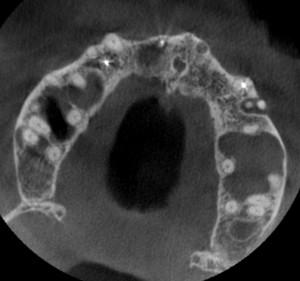

根っこの治療が終了してから半年。ほぼ同じ部位での水平断。膿の袋は縮小傾向に見える。

根管治療半年後。膿の袋は縮小傾向にあるように見える。Bさんは、「インプラントはやってほしいけど、別に急ぎませんから」と、いつもおっしゃっていただいているので、もう少し待つべきか? 全然術前と変わっていなければ、外科的に膿の袋を取ってしまおうと思っていたが、一応改善がありそうなので、CT像で骨が溶けてる部分(黒い部分)が再生して、白く見えてくるまでは待ってみるか。(長谷川)